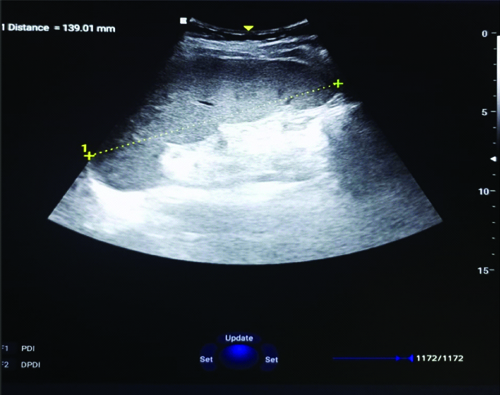

Ultrasound of the abdomen confirmed splenomegaly (8 cm in size along the longest axis) [Table/Fig-6].

USG Abdomen showing splenomegaly of 13 cm.